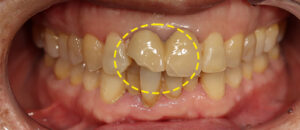

해당 환자분께서는 기존 앞니 보철 파절 선이 있으며,

옆의 치아도 깨짐이 있는 상태였어요. 😭

기존 보철물은 과거 보철치료 시

많이 사용했던 PFM 이란 보철로,

시간이 많이 경과할 경우 잇몸에

까맣게 비치는 것이 단점인 재료였답니다.

이를 개선하기 위해 연세에이스치과에서는

앞니에 올세라믹 크라운 치.료를 진행하였고

앞니 옆의 치아는 손상의 범위가 좁은 편이라

레진을 이용한 심미수복으로 결정을 하였어요.